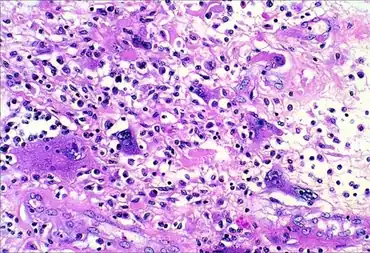

| Micrograph of undifferentiated pleomorphic sarcoma (H&E stain) | |

UPS is a diagnosis of exclusion (a diagnosis reached by the process of elimination) because the histopathology of this disorder's tumors is non-specific. UPS tumor cells are undifferentiated (i.e. do not resemble any particular cell type) and pleomorphic (i.e. highly variable in size, shape, and/or color) when examined microscopically. Therefore, the diagnosis of UPS is commonly based on detecting a specific set of proteins that are expressed by UPS tumor cells but not by the cells of other undifferentiated and pleomorphic tumors or visa versa (see Diagnosis section).[11]